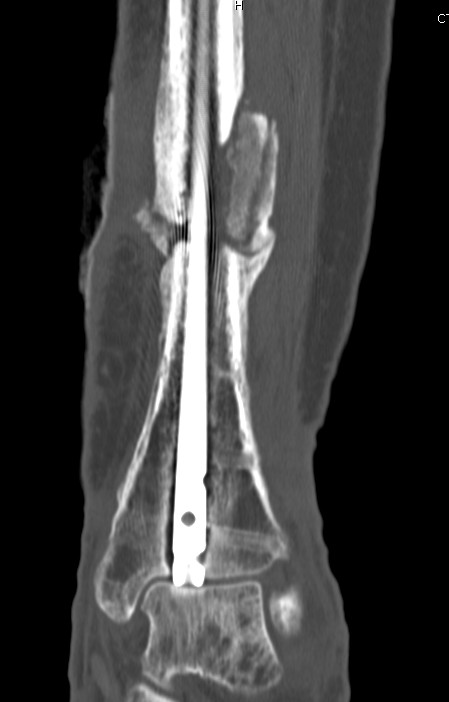

Case

12 months of persistant sinus drainage

- nail removed

- Ilizarov applied with fibular osteotomy and acute compression of non union

- 6/52 IV Abx

Infected Tibial Non Union XrayInfected Tibial Nonunion CT

Infected Tibial Non Union Ilizarov APInfected Tibial Non Union Ilizarov Lateral